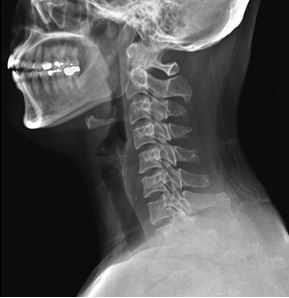

그림3.png 촬영 일시: 2025.03.04

<Fig 1. 목 X-Ray 영상>

손목터널증후군이 아닌

목디스크로 인한 신경근 압박이

팔저림과 손저림의 진짜 원인이었던 거죠.